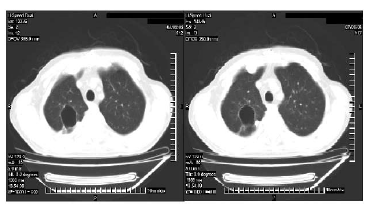

Figure 4. A thoracic computed tomographic scan showing the posttreatment decreased dimensions of the nodules and cavity, the regression of parenchymal consolidation, and the resolution of the aircrescent sign in the cavitation.

Signs of acute rejection were observed during the third posttransplant month in a 47-year-old man who, at our institution in September 2007, received an orthotopic heart transplant as treatment for dilated cardiomyopathy. This patient’s laboratory test results were seronegative for CMV during the pretransplant period, but the CMV serologic status of the donor was unknown. The patient was treated with cyclosporine (15 mg/kg) and mycophenolate mofetil (2 × 1.5 g) and received prophylaxis against CMV (intravenously administered ganciclovir (2 × 5 mg/kg induction treatment for 2 weeks and 2 × 2.5 mg/kg maintenance treatment) for 1 month and oral valganciclovir (2 × 450 mg) for 2 months as a standard posttransplant regimen. To treat rejection, he received pulsed steroids, a few days after which dyspnea, cough, purulent sputum, and a fever of 38.5ºC developed. The patient was diagnosed as having pneumonia, and treatment with ceftriaxone (1 × 2 g intravenously administered) was initiated. That initial treatment was replaced with piperacillin-tazobactam (4 × 4.5 g intravenously administered) anti¬biotic therapy because tachycardia (102 beats/min), tachypnea (22 breaths/min), and fever persisted, and the patient’s orientation and ability to cooperate deteriorated. The results of biochemical testing revealed the following values: white blood cell count, 5.1 × 109/L; hemoglobin value, 8.3 mmol/L; platelet count, 14 × 109/L; aspartate transaminase, 74 U/L; alanine transaminase, 46 U/L; alkaline phosphatase, 2972 U/L; γ-glutamyltransferase, 803 U/L; L-lactate dehydrogenase, 2177 U/L; total bilirubin, 61.1 µmol/L; and direct bilirubin, 44.3 µmol/L. Treatment with ganciclovir 2 × 5 mg/kg was added to the regimen because the patient exhibited bicytopenia; elevated liver enzymes; cerebral symptoms; and the following values: CMV pp65 antigen, > 8 antigen-positive cells/2 × 105 peripheral blood leucocytes; and CMV real-time polymerase chain reaction results, 31 245 copies/mL, all of which indicated CMV infection. Bronchoscopy was not performed because of the patient’s severe thrombocytopenia, and the histopathologic findings did not confirm CMV pneumonia. Extended spectrum beta-lactamase–producing Klebsiella pneumoniae was grown in the sputum culture, and piperacillin-tazobactam was replaced with carbapenem Meropenem (3 × 1 g intravenously administered). Despite treatment with ganciclovir and the meropenem, the patient required increasing support with oxygen and exhibited progressive dyspnea. A posteroanterior radiograph of the chest revealed pulmonary infiltration and a cavitary lesion in the superior lobe of the right lung (Figure 1). A thoracic computed tomographic scan showed bilateral nodular lesions with a halo sign, consolidated areas, and a cavitation (23 × 19 mm) in the superior lobe of the right lung (Figure 2). Coinfection with Aspergillus was suggested by the thoracic computed tomographic findings, and a galactomannan antigen index of 2.3 supported that diagnosis. Blood samples for serum galactomannan antigen levels were obtained 6 hours after the last administration (and just before the next administration) of the piperacillin-tazobactam infusion to prevent possible false-positive results. The patient was diagnosed as having probable invasive pulmonary aspergillosis and received parenteral voriconazole (a 2 × 6 mg/kg loading dose followed by a 2 × 4 mg/kg maintenance dose). His dyspnea, fever, and biochemical parameters were within normal limits at follow-up. Treatment with the meropenem was discontinued after 2 weeks and ganciclovir therapy was terminated after 4 weeks as the test results for CMV pp65 antigen and the CMV real-time polymerase chain reaction became negative. At the follow-up examination, the patient’s galactomannan levels had also decreased (Figure 3), and a control thoracic computed tomographic scan revealed the decreased dimensions of the nodules and cavity, the regression of parenchymal consolidation, and the resolution of the air-crescent sign in the cavitation (Figure 4). The radiologic findings are shown in Figure 2. The patient’s antifungal treatment was changed to oral voriconazole (2 × 200 mg), which was continued until all abnormal radiologic findings had resolved.